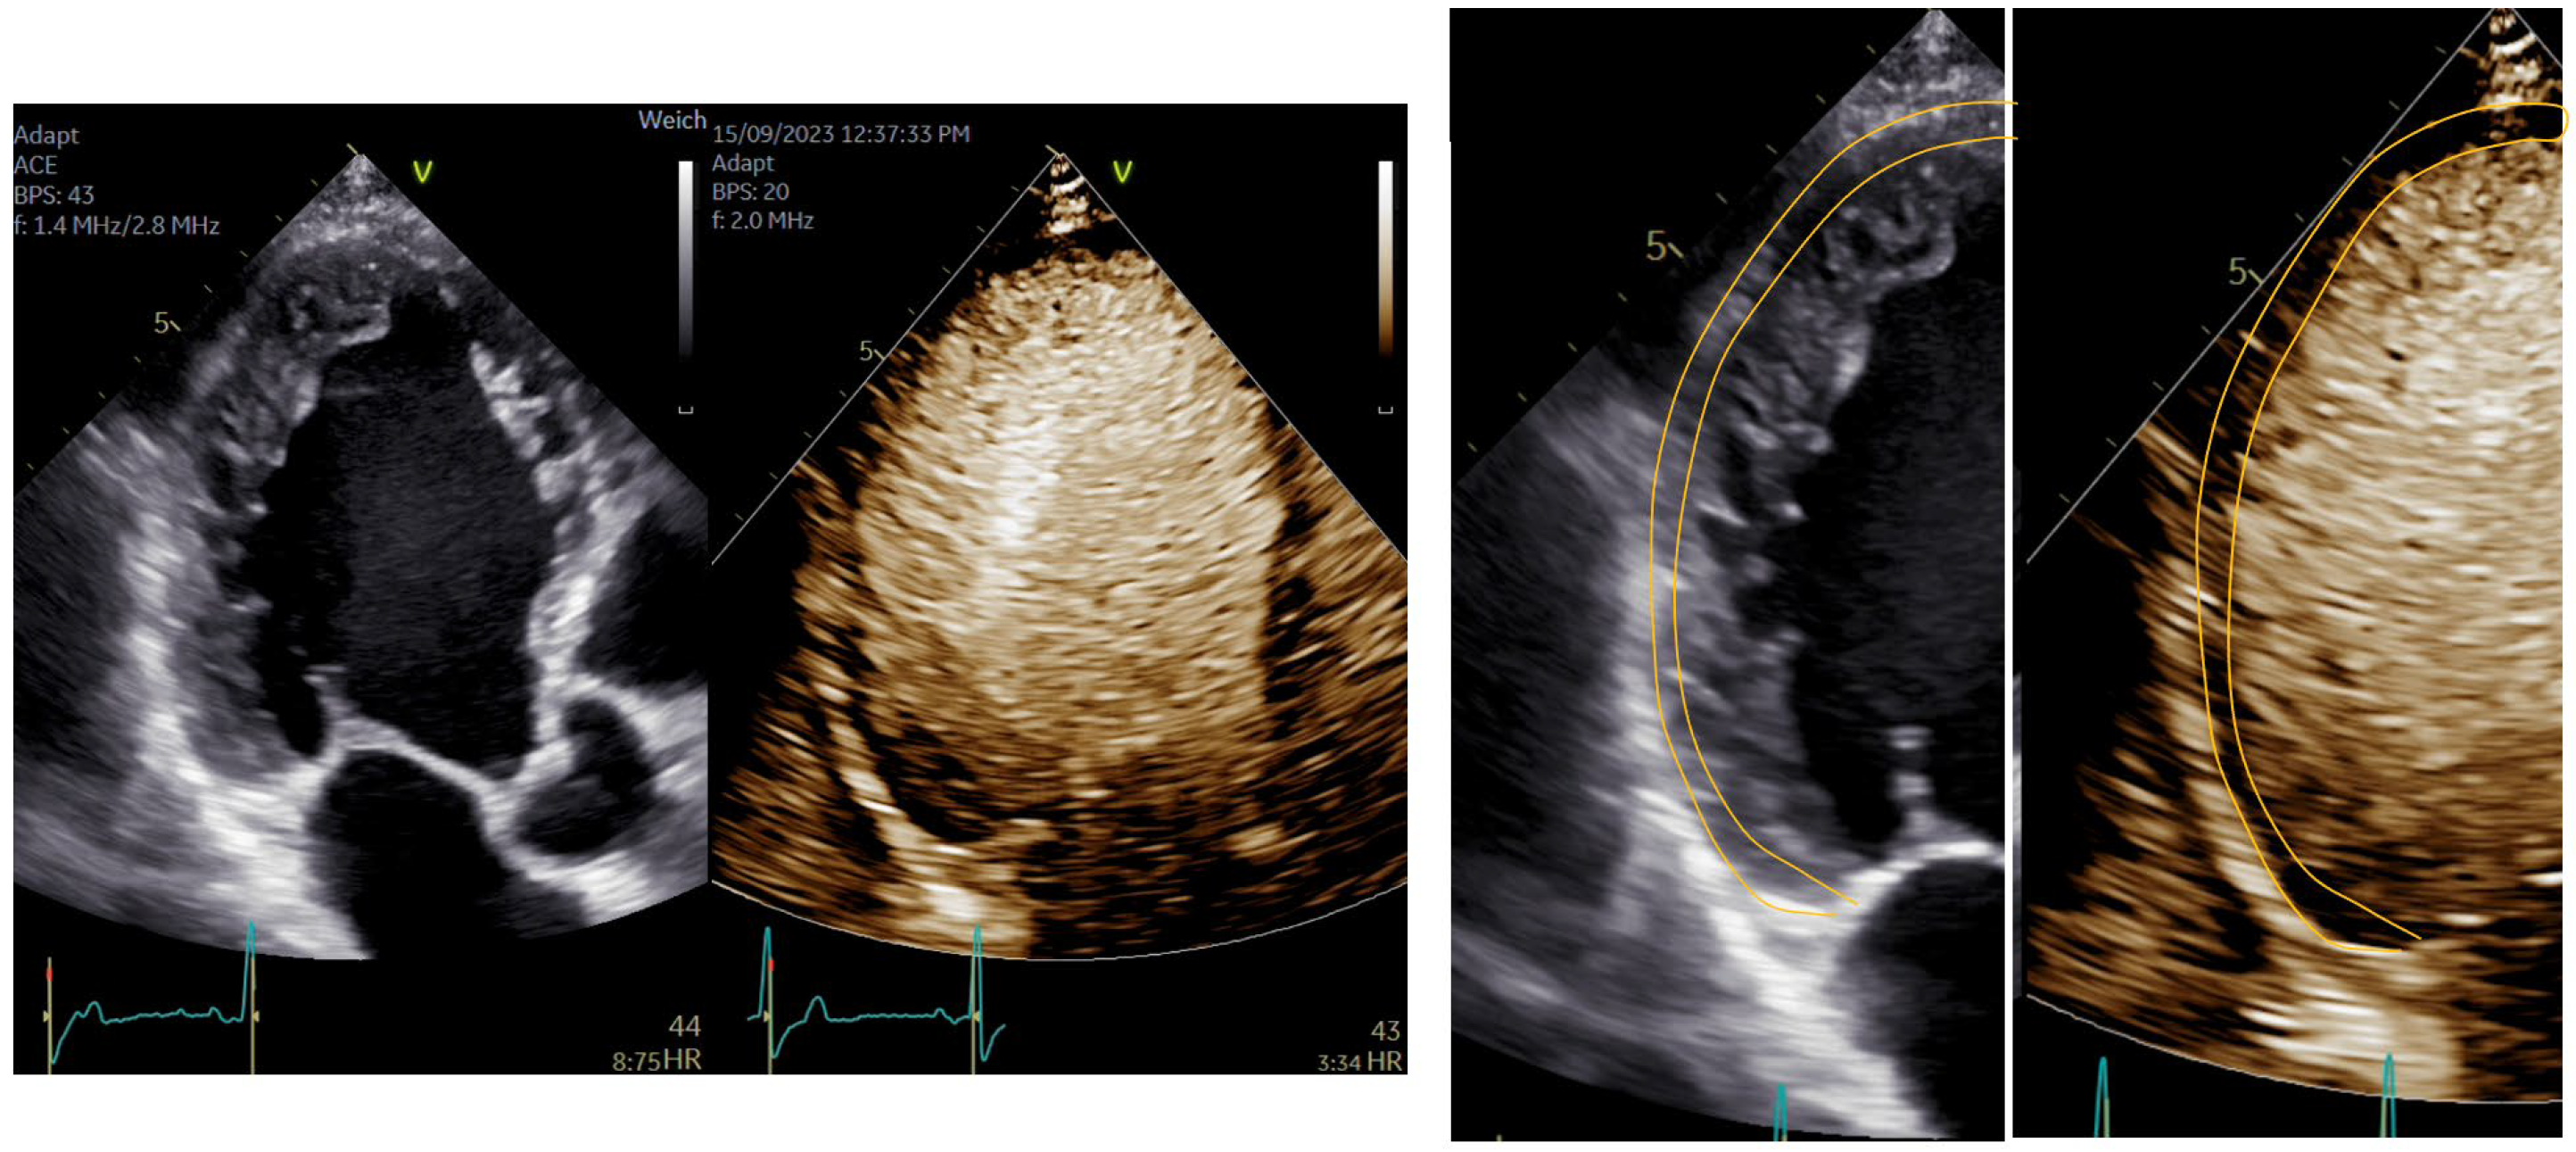

| Imaging method | start with low-MI-contrast-specific imaging for assessment of global and regional LV function then use intermediate-MI-contrast-specific imaging which provides better display of LV trabeculations |

| Imaging planes | standard apical views parasternal and apical short-axis view |

| Contrast application | bolus injection |

| Typical findings | trabeculated layer apical, lateral, and inferior: more than 3 trabeculations, ratio of trabeculated/compact myocardium >2 The number of trabeculations and the ratio of trabeculated/compact myocardium does not seem to impact clinical management |

| Alternative imaging | MRI for tissue characterization in dilated cardiomyopathy and risk assessment in hypertrophic cardiomyopathy, assessment of LV thrombi when CEUS recordings are non-diagnostic |